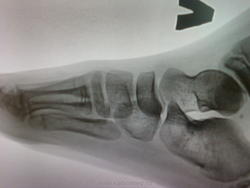

Уважаемые коллеги, подскажите пожалуйста. Девочка 7 лет. Настрожили "изменения" в ладьевидной кости. На обычных снимках смотрится как небольшая узура по медиальной поверхности. Но на  цифре вроде не очень заметно. Привожу цифровые снимки, обычный к сожалению выложить невозможно. На другой стопе ничего такого нет. Или это игра теней?

криминала вроде не видать..

и в клиновидной кости то же